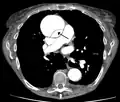

Computed tomography

Computed tomography angiography is a fast, non-invasive test that gives an accurate three-dimensional view of the aorta. These images are produced by taking rapid, thin-cut slices of the chest and abdomen, and combining them in the computer to create cross-sectional slices. To delineate the aorta to the accuracy necessary to make the proper diagnosis, an iodinated contrast material is injected into a peripheral vein. Contrast is injected and the scan performed using a bolus tracking method. This type of scan is timed to injection to capture the contrast as it enters the aorta. The scan then follows the contrast as it flows through the vessel. It has a sensitivity of 96 to 100% and a specificity of 96 to 100%. Disadvantages include the need for iodinated contrast material and the inability to diagnose the site of the intimal tear.

-

CT with contrast demonstrating aneurysmal dilation and a dissection of the ascending aorta (type A Stanford) -

Chest CT with descending (type B Stanford) aortic dissection (red circle)

Type A dissection with pericardial effusion as a result.